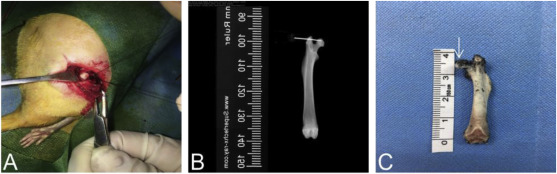

创伤性ONFH的建立及唑来膦酸治疗组:22只大鼠腹腔注射2%戊巴比妥(0.3ml/100g)麻醉后,置于手术台上。大鼠被深度麻醉后对手术区域进行备皮。对皮肤消毒并用无菌手术巾覆盖。 从大转子中心大约2厘米长的地方做一个右髋关节外侧切口。分离肌肉,沿肌纤维方向牵拉,切开髋关节囊露出股骨头,髋关节脱位,用3-0缝线紧紧围绕股骨头底部切断圆韧带,左、右滑动5次,破坏股骨头供血。为了确保足够的唑来膦酸保留在股骨头中,用2毫升注射器的针头插入约0.2厘米长,给每只大鼠注射约100μL(4mg/5ml)唑来膦酸。手术过程中绕过坐骨神经,避免损伤,强化关节囊,保持髋关节周围肌肉的完整性,避免髋关节脱位。为防止感染,用生理盐水冲洗伤口,然后将切口分层缝合。所有大鼠醒来后,均活动自如,进食无异常。

图1、外伤性ONFH的建立过程和注射唑来膦酸的途径。

图2、将墨水注入正常股骨头以验证使用相同的方法唑来膦酸也可以成功应用。 B.在X射线下; C、注射墨汁后股骨头的冠状面。